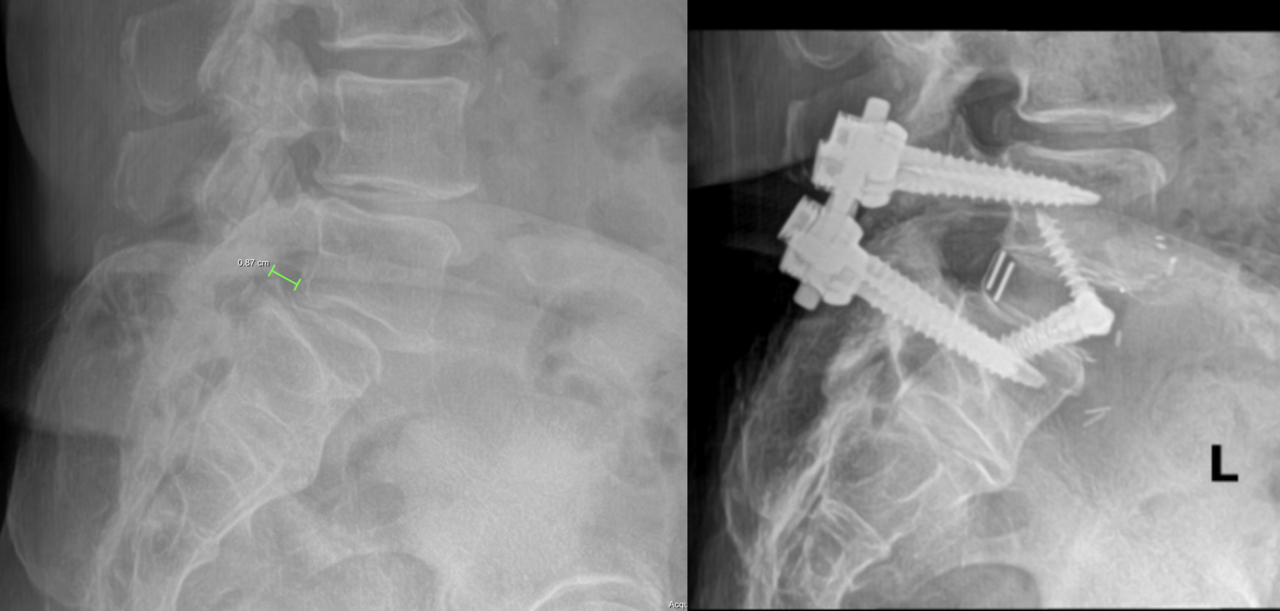

Anterior lumbar disectomy and intervertebral fusion (ALIF)